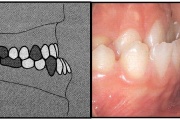

Esimese jäävmolaari ektoopiline lõikumine

Ravijärgne seis. Jäävhammas on täielikult lõikunud.

) Röntgenülesvõte. Ülemise esimese jäävmolaari lõikumine on takistatud 2. piimamolaari tõttu